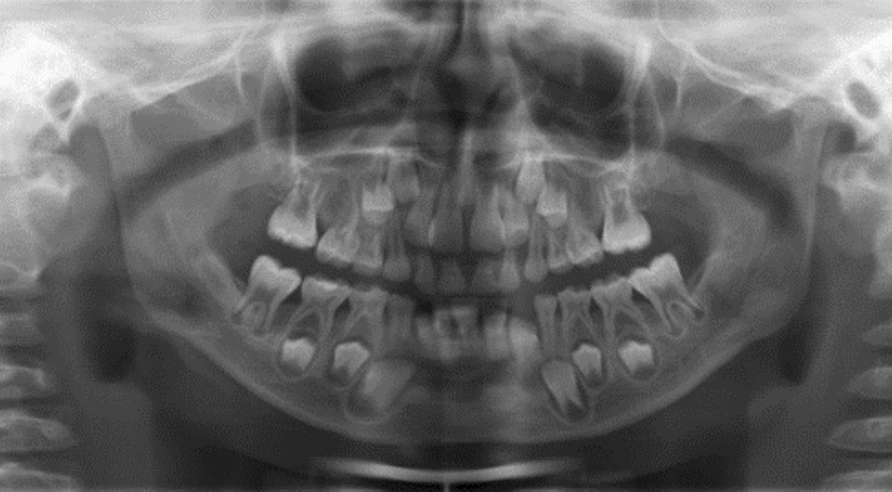

Case presentation: A 6-year-old girl of Swedish descent was referred for evaluation owing to bleeding gums and oral discomfort. Clinical examination revealed dry, cracked lips, inflamed oral mucosa and gingiva, carious primary teeth, and multiple missing permanent teeth. Treatment was performed under general anesthesia, and the patient was placed on a bi-monthly follow-up schedule. After 2 years, her oral health had significantly improved.